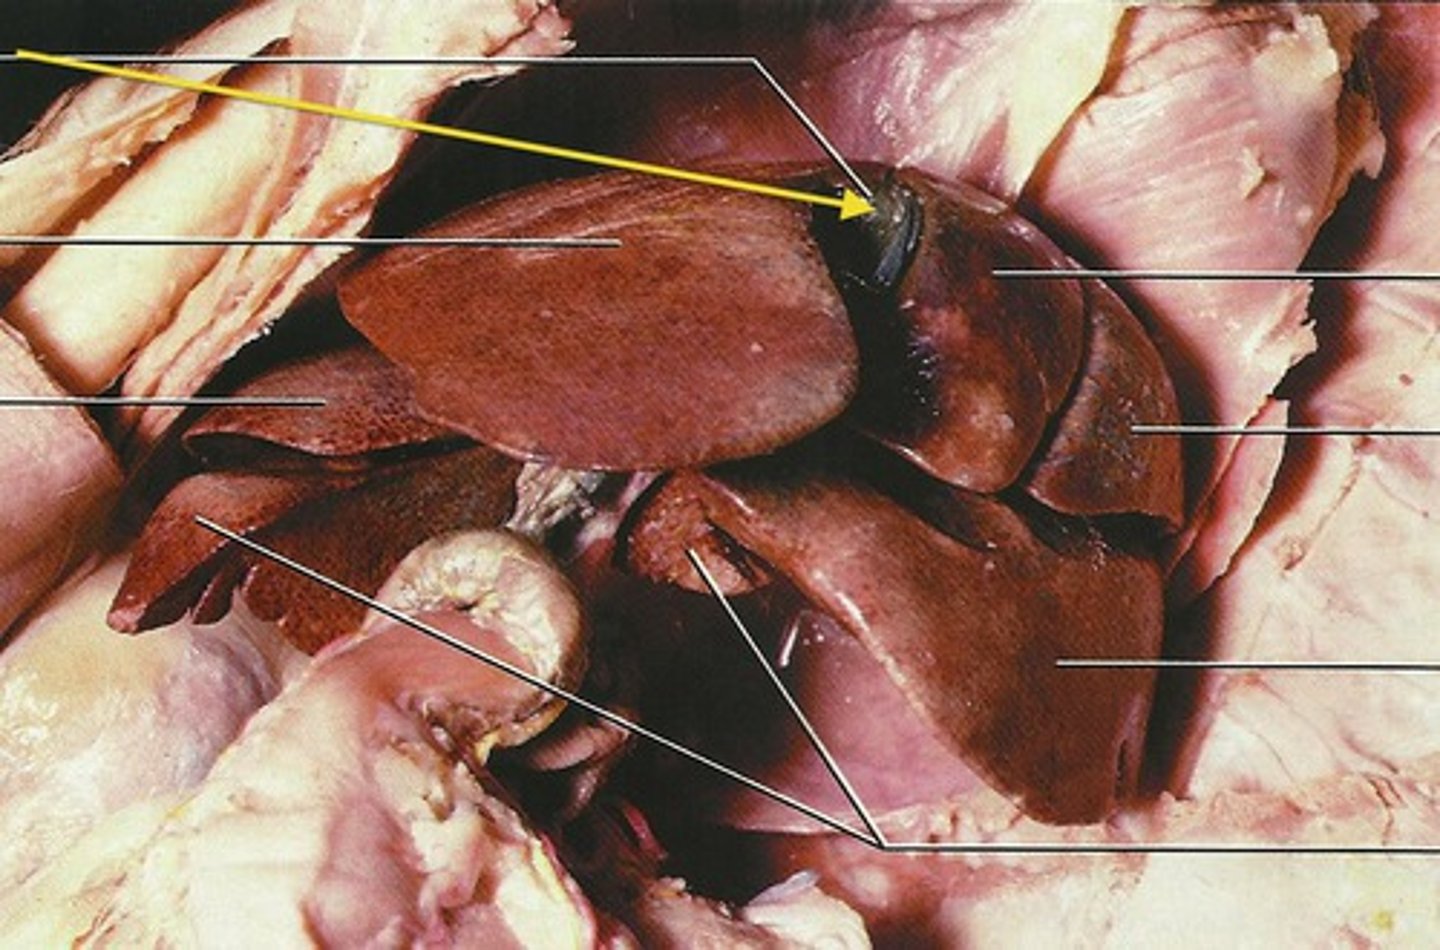

diaphragmatic surface (of spleen)

spleen

produces, stores, and eliminates blood cells

pancreas

visceral surface (of spleen)

hilum (of spleen)

splenic vein

right lobe (of liver)

left lobe (of liver)

quadrate lobe (of liver)

caudate lobe (of liver)